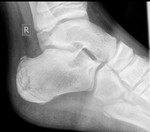

Давнишнее исследование. Уж 3 года как. Случай коллеги. Подросток, 15 или 16 лет. Болит пятка.

Хаглунда-Шинца болезнь (остеохондроз апофиза пяточной кости) - вариант остеохондропатии апофизов в бугре пяточной кости.

Рентгеновская диагностика. При болезни Шинца на снимке будет наблюдаться пятнистость паточной кости и отсутствие гомогенности тени ее бугра. В некоторых случаях возможно наличий отложения солей, которые видны как небольшие островки. При тяжелых формах заболевания отчетливо просматриваются такие рентгенологические признаки как отделение фрагментов краевой кости и увеличение расстояния между пяточной костью и апофизом.

Также стоит учесть, что для исключения множества других заболеваний (пяточная шпора, остеомиелит, туберкулез пяточной кости, периостит, ахиллобурсит и т.д.) необходимо проведение дифференциальной диагностики.

Снимки интересные, ничего не скажешь. Но топикстратер говорил о ребенке 10 лет. А в вашем случае, явный взрослый. Может, есть смысл о синдроме Хаглунда говорить в этом случае.

1. пятнистость и негомогеннность указывал Рейнберг ещё, но и про секвестроподобность оных писал( т.е. не просто пятнистость и гомогенность.)

2. островки отложения каких-то солей? Рейнбергом описано так, то что имеется в энтом апофизе несколько точек окостенения, числом до 3-4! И при этом они не имеют правильной формы и контуры не гладкие и м.б. и зазубренные!(т.е. всякие)

3.увеличение расстояния между пяточной костью и апофизом? Так вот дедушка пишет, что это разрастание!!!( не хондроз!или дегенерация) хряща.

4. По поводу приведенных снимков: очень интересная картина АХИЛЛОБУРСИТА+ пяточного бурсита (. Т.е. требует дифф. диагностики... )

5. Коллега, Андрей Юрьевич, справедливо заметил, что приведенные снимки скорее относятся к деформации или болезни Хаглунда. http://www.travmaorto.ru/139.html а не к б-ни Шинца.